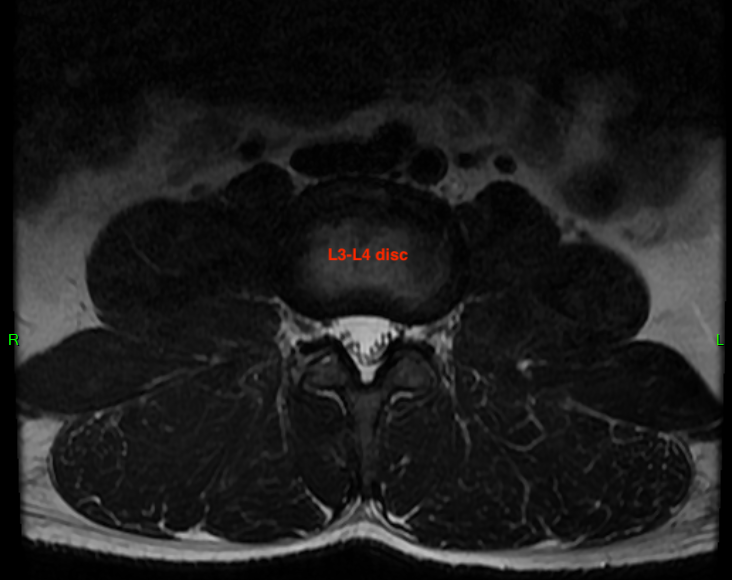

I want to show three levels for comparison. These are disc-level slices of my L3-L4 IVD, which is healthy. I've drawn cut lines on each image to show you how the slices correlate. These are T2-weighted images, which means water is hypersensitive (bright white). Tissue with high water content shows up as lighter, and you can see my relatively healthy IVDs all have a light center. That's because the nucleus pulposus is about 80% water and is responsible for about 80% of the axial load bearing of the spine. The remaining 20% of axial load is absorbed by the facet joints, which are a pair of hinge-like joints connecting adjacent vertebrae. They "fasten" the spine together and prevent excessive bending and twisting.

(L3-L4 Axial MRI)

This correlates on the axial view. The bright white triangle is the thecal sac and the black dots inside it are the cauda equina nerves. These nerves will exit from the thecal sac and pass through the neural foramen, a hole between two verbebrae. These holes are relatively small, but in a healthy person, there's plenty of space for the nerve roots to pass through without compressive forces.